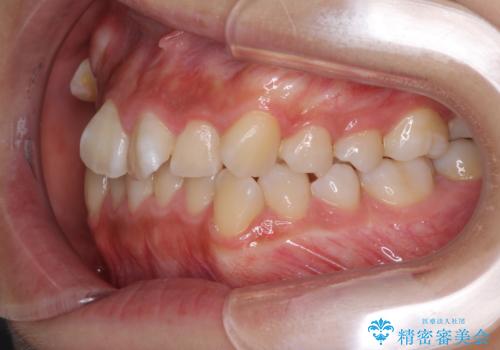

- 前歯のでこぼこと乳歯が残るほどの八重歯を気にして来院された患者様です。

非抜歯にてワイヤー矯正にて治療することとしました。(ただし、親知らずと乳歯は抜歯)

犬歯は歯根が太く長いため、移動には時間を要します。しかし、犬歯は機能面から考えて残すことを選択したいため、長期間をかけて治療を行うこととしました。

治療の度に歯列が改善していったため、長期間の治療も楽しく過ごしていいただき、満足のいく仕上がりとなりました。